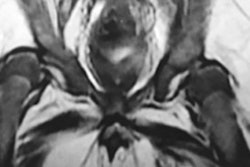

Demand is growing for emergency CT scans of the cervical spine, and because many examinations are performed at night or on weekends, often radiology trainees end up reporting them, U.K. researchers said. To speed up patient care and cut errors, they looked at how to improve training in this area, focusing on seven key learning points. Click here to find out more.